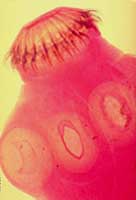

Sán dây trưởng thành:thường dài 2-4m, có khi dài tới 8-10 m. Nhìn bên ngoài sán dây có hình thể như một dải băng và có 3 phần: phần đầu là một hình cầu mang những mồm hút và bộ phận bám, phần cổ thường thắt lại và không có đốt, thân gồm nhiều đốt và những đốt tuỳ theo độ trưởng thành có sự phát triển khác nhau. Au trùng sán dây lợn: khi phát triển đầy đủ, ấu trùng là một túi giống như một hạt đu đủ mọng nước, chiều dài 15mm, chiều ngang 7-8mm, hình dạng của ấu trùng có thểthay đổi tuỳ theo nơi ký sinh. Ở những cơ chắc, ấu trùng có hình kéo dài, nhưng ở những bộ phận có tổ chức lỏng lẻo ấu trùng có hình cầu.

Đầu sán dây | Đốt sán dây | Trứng sán dây |